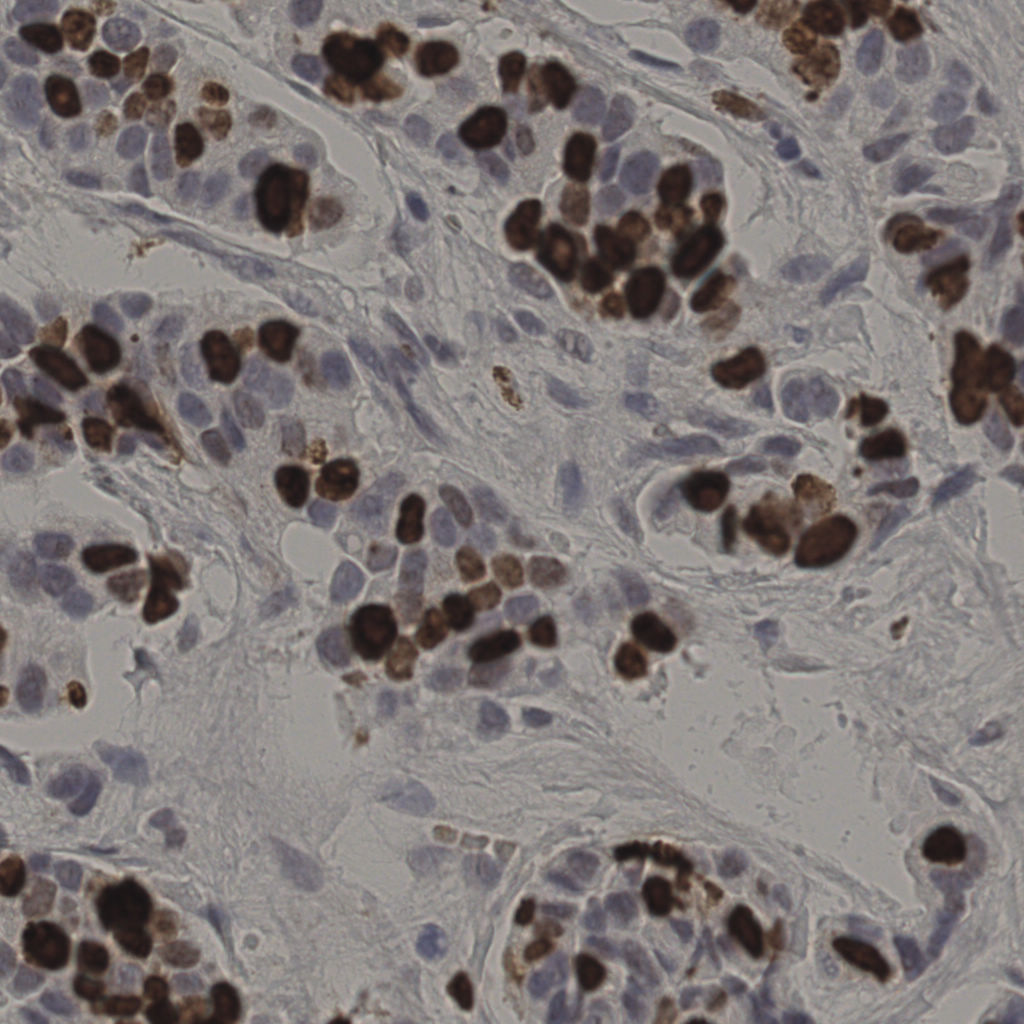

17.75%

Ki67 指数

阴 7986

阳 1723